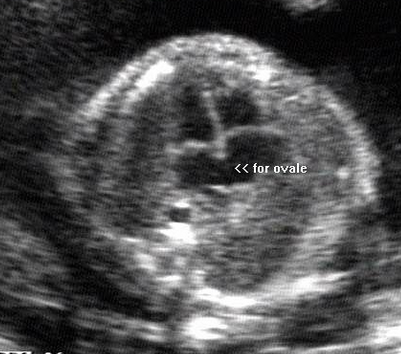

What is the feral lie based on the anatomy showed?

Breech spine up